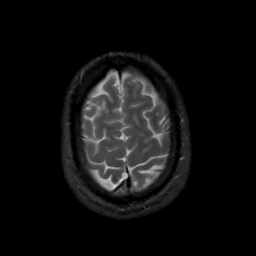

MR Study #13, May 19, 1991 -- Slice #43

[Home][Help][Clinical][Tour 1][Tour 2] Slice 43